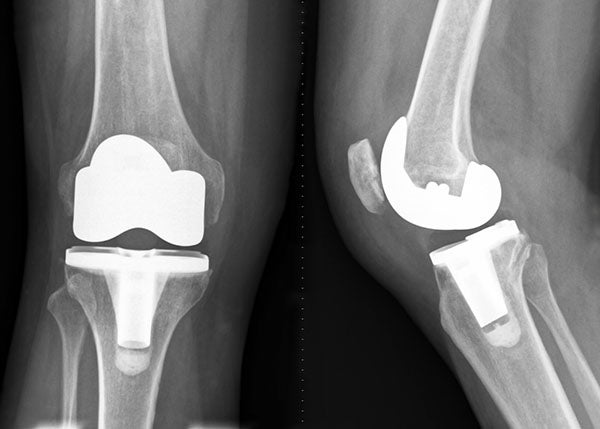

Knee Replacement

knee replacementThe knee joint consists of a layer of smooth cartilage on the lower end of your femur (thighbone), the upper end of the tibia (shinbone) and the undersurface of the patella (kneecap). This cartilage serves as a cushion and allows for smooth motion of the knee. Arthritis is a wearing away of this cartilage, which eventually wears down to bone. Rubbing of bone against bone causes pain, swelling and stiffness. For patients with significant arthritis who have failed conservative treatment, your surgeon may recommend joint replacement surgery.

Surgeons don’t actually replace the joint as is commonly thought. Instead, your surgeon replaces the damaged cartilage found at the end of the bones in your knee joint. This is done with a metal alloy on the femur (thighbone) and a medical grade plastic spacer on the tibia (shinbone) and patella (kneecap). This creates a new smooth cushion and a functioning new joint. The implants are designed to restore function and eliminate as much discomfort as possible while allowing the patient to return to a more active lifestyle.